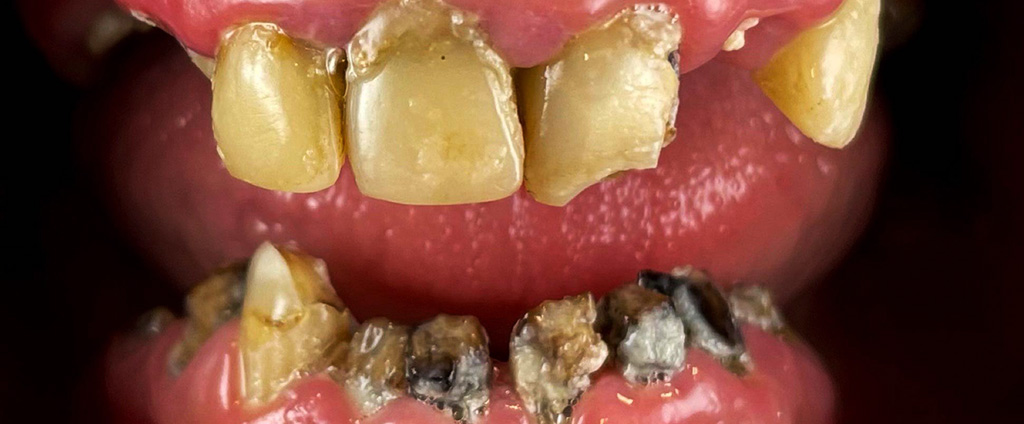

1. Konsultacja z ekspertem

Podczas pierwszej wizyty lekarz implantolog wykonuje badanie wewnątrzustne, tomografię komputerową (CBCT) podczas której, weryfikuje ilość oraz jakość kości wyrostka zębodołowego. Jeśli z powodu znacznej atrofii wykonanie metody All-on-6 okaże się niemożliwe zaproponujemy inne rozwiązanie. Konsultacja taka kończy się wykonaniem planu leczenia wraz z kosztorysem.